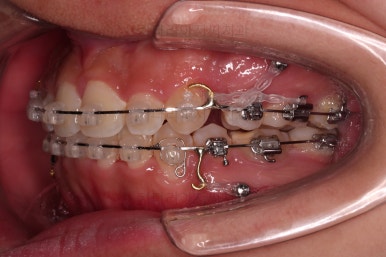

초진 시 입안의 모습입니다.

앞니가 많이 삐뚤고, 송곳니가 부각되어 덧니처럼 보이네요.

장치를 처음 부착한 모습입니다.

이번 환자분이 선택하신 장치는 데이몬 클리어라고 하는 자가결찰 세라믹 장치인데요.

흔히들 아시는 클리피씨 장치 등등에 비해 현존하는 브라켓 중에 가장 심미적인 장치입니다.